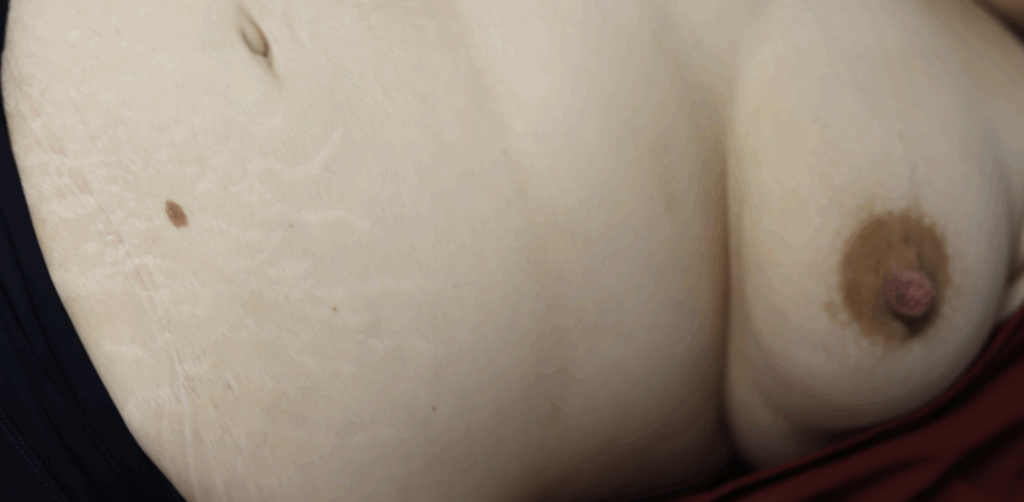

Nipples at 39 weeks and 3 months

Patient who underwent partial excision of left nipple adenoma three months prior to pregnancy. She breastfed using a nipple shield to reduce trauma to the residual adenoma on the left nipple (which bled with trauma) and did not use a nipple shield on the right breast.